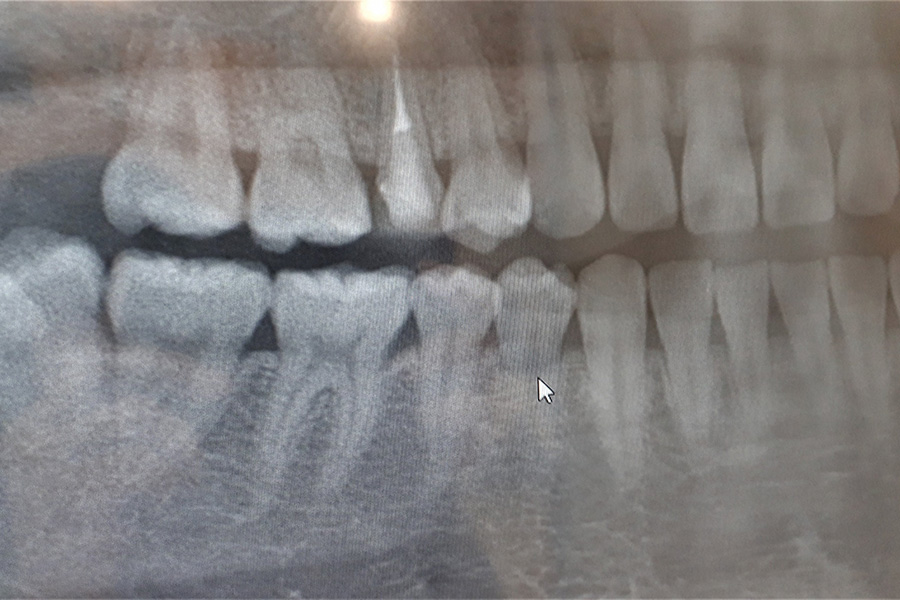

当院では必要に応じて歯科用レントゲンを活用し、歯の根や親知らずの状態を把握したうえで、正確な診断と処置を行っています。当院での処置が難しい手術が必要となる場合には、適切な医療機関をご紹介させていただきます。

親知らずとは、10代後半から20代にかけて生えてくる奥歯のことです。

あごのスペースが足りず、斜めや横向きに生えるケースも多く、周囲の歯に悪影響を及ぼすことがあります。違和感や痛みがある場合は、早めに受診して状態を確認しましょう。